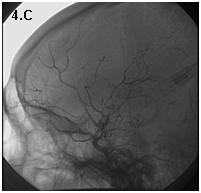

Mujer de 46 años que ingreso por cefalea súbita, hemiparesia izquierda y disartria, con tomografía axial computarizada cerebral simple que mostró hemorragia frontoparietal derecha drenada a ventrículos y arteriografía con patrón Moyamoya. Reingreso 3 meses después con deterioro del estado de consciencia y tomografía axial computarizada cerebral simple que mostró hemorragia intraparenquimatosa temporoparietal izquierda con extensión intraventricular y desviación de la línea media, se manejo en Unidad de Cuidados Intensivos con traqueostomía y gastrostomía, presentó neumonía y sepsis nosocomial, finalmente falleció en la Unidad de Cuidados Intensivos.